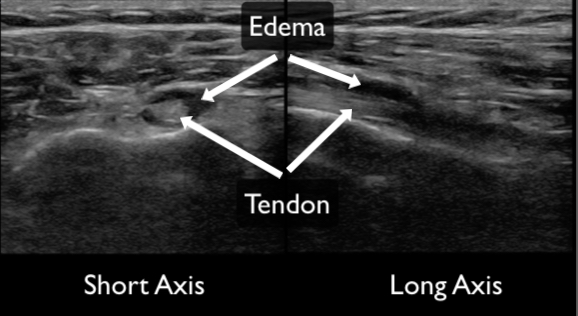

Tendons should be interrogated in their entirety in the short and long axis to where they insert into the bone. The region adjacent to bony insertion is where the majority of pathology is identified. Complete or partial ruptures are readily apparent as disruption of normal striated tendon fibers often with associated surrounding hematoma (Figures 11, 12 & 13). Range of motion testing with simultaneous ultrasound can assist in evaluation for complete ruptures. Tendinopathy can be identified by the presence of calcifications (Figure 14), edema (Figure 15), and increased vascularity (when compared to the contralateral tendon). Edema will make the tendon more hypoechoic and larger in diameter compared to the contralateral tendon.

Figure 15. Tendinosis with surrounding edema demonstrated in both the short (left) and long axis (right). The edema appears as a hypo or anechoic ring around the tendon.